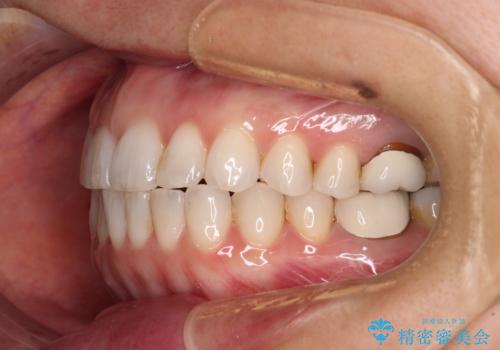

- 前歯のデコボコと上下スペースと前歯の隙間を気にして来院された患者様です。

目立たない装置を希望とのことでインビザラインにより、デコボコを解消しつつ、上下の前歯の隙間を閉じていくこととしました。

デコボコはあっという間に解消されましたが、上下前歯の隙間がなかなか解消されませんでした。

飲み込みの際に舌を前方に突出する癖があり、飲み込みの度に前歯に強く接触していたため、上下前歯の隙間が維持されていました。

舌の訓練を徹底していただいたことで、徐々に隙間は解消され、きれいな歯列に整えることができました。